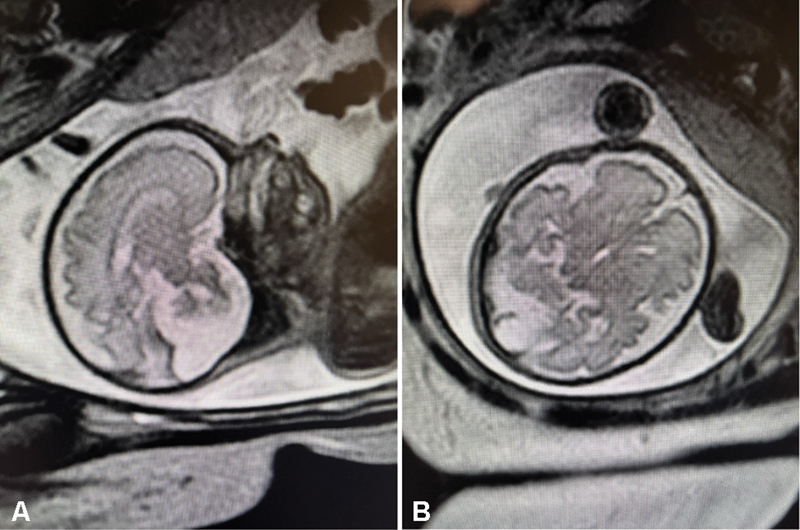

背景:很少有与努南综合征(NS)相关的Dandy-Walker畸形的报道。病例介绍:我们在此提出一个患有Dandy-Walker畸形(DWM)的晚期早产儿的病例,该婴儿接受了喂养困难的检查,并被发现患有NS。这是少数报道的DWM合并NS具有PTPN11基因突变的病例之一。结论:重叠的临床特征可能会掩盖婴儿多重病理的诊断。

Background: There are few reported cases of Dandy-Walker Malformation associated with Noonan syndrome (NS).

Case presentation: We herein present a case of a late preterm infant with Dandy-Walker malformation (DWM) that underwent a workup for feeding difficulty and was found to have NS. This is one of the few reported cases of DWM with NS having a PTPN11 gene mutation.

Conclusion: Overlapping clinical features may disguise diagnosis in infants with multiple pathologies.